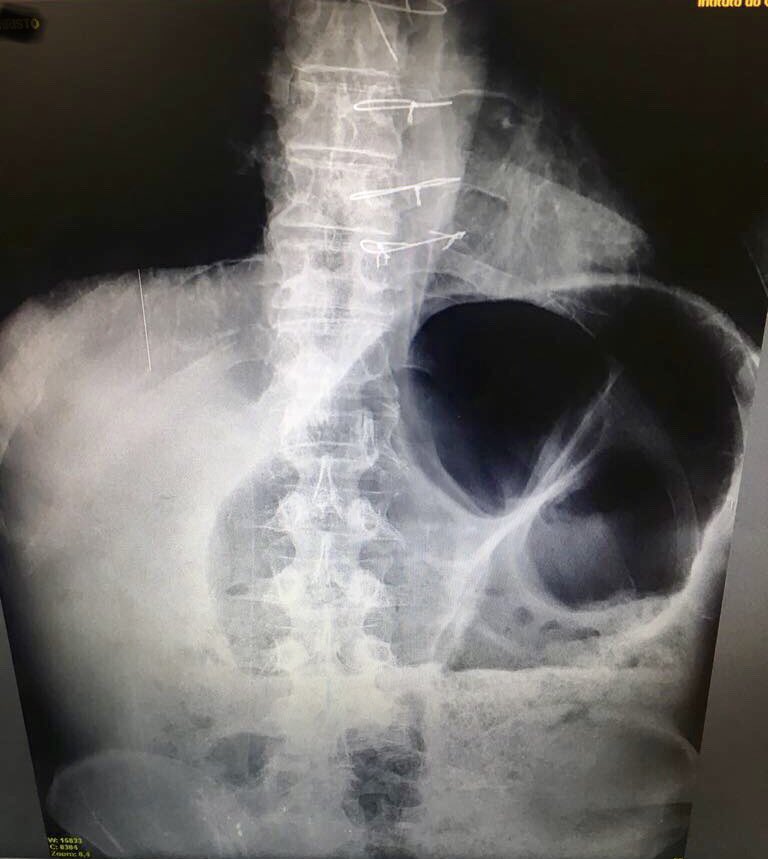

Intestinal Volvulus in a Heart Transplant patient. Classical image!

#HeartTransplant pic.twitter.com/rU80teFpUw